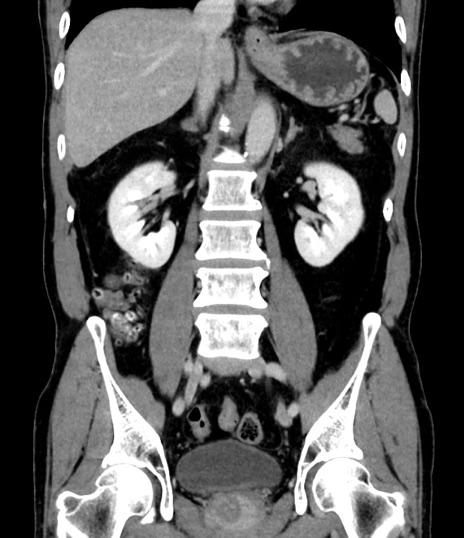

症例8(冠状断像)

【症例】 60歳代男性

【主訴】 黒色吐物

【現病歴】 4日前から嘔気自覚、2日前の朝食後にも嘔気あり、自分で手で嘔吐反射起こし嘔吐したところ血が混ざっていたため受診。

【既往歴】 5年前汎発性腹膜炎を伴う急性虫垂炎で手術、高血圧、前立腺肥大症、高脂血症

【身体所見】 腹部正中に手術癩痕あり 腹部平坦・軟圧痛なし膨満感あり

【データ】WBC 8400、CRP 4.54